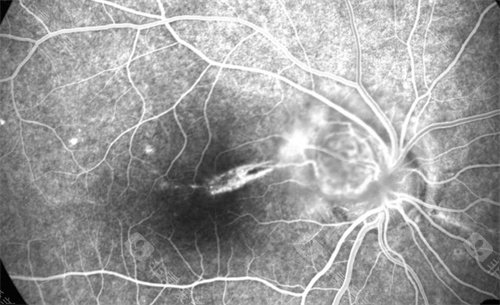

医院引进了一系列靠前的眼底病检查和治疗设备,如光学相干断层扫描(OCT)、眼底荧光血管造影(FFA)等,这些设备能够为医生提供精密的诊断依据。